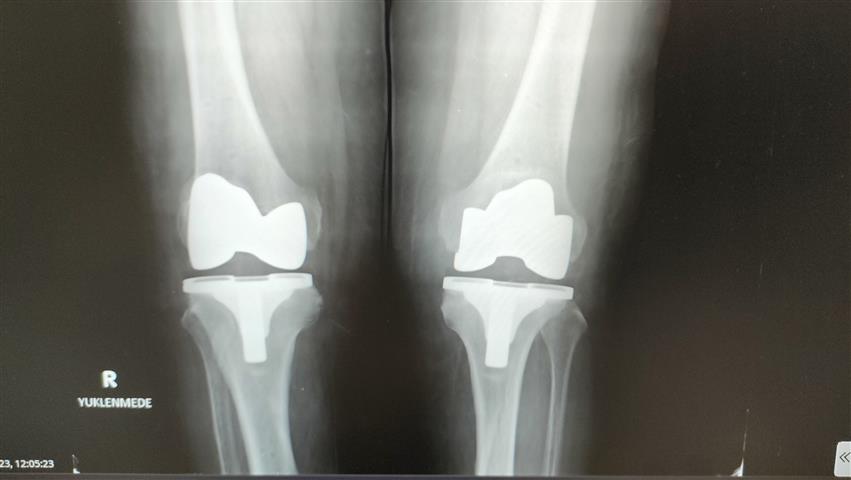

Çoğu hasta grubumuz böyle. Robotik protezler diğer protezlere göre şöyle bir farklılığı var; biz bu protezi hastaya özel ürettiriyoruz. Ameliyat öncesinde tomografi ve filmler sisteme yükleniyor. Sistem sayesinde protezler hastaya özel üretildiği için, kişiye özel olarak gelmiş oluyor. Bu protezi robotik yardımlı olarak ameliyatta hastaya uyguluyoruz. Bu işlem kabaca yarım saat 45 dakika sürüyor” dedi.

Hastanın bir iki gün hastanede kaldıktan sonra yürür şekilde taburcu olduğunun altını çizen Baloğlu, “Bu ameliyatta daha az kesiden işlem yapıldığı hem de hastaya özel protez kullanıldığı için hata payımız neredeyse sıfır. Bu nedenle hasta da bir ay sonra geçirdiği bu işlemi neredeyse unutmuş olur.

Yürüme sıkıntısı çeken hasta rahatlıkla yürüyerek çıkıyor. Çünkü ağrı olmadığı zaman hasta zaten yürümek istiyor ve bunu biz de talep ediyoruz. Dolayısıyla bundan sonrasında, ‘aman yürüme üzerine basma’ demiyoruz. Tam yükle mobilize olur şekilde hasta gidebilir buradan.

Özellikle namaz kılma noktasında zorlanan yaşlılarımızdan çok soru geliyor. Robotik protezlerin dizaynında mobil dediğimiz hareketli protezlerde namaz kılma anlamında bir engel durum yok. Biz bunu gerekli rehabilitasyon yapıldıktan sonra hasta sandalye ya da başka bir şey kullanmadan namazını kılabilir” ifadelerine yer verdi.